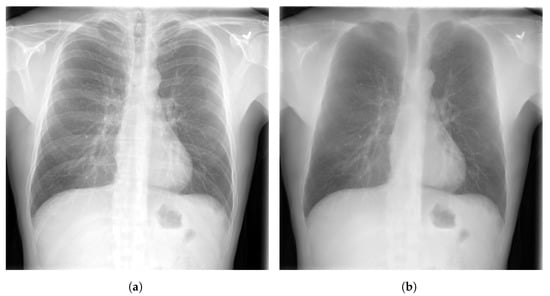

- ChestX-ray14 [39] is a dataset of images extracted from the PACS (Picture Archiving and Communication Systems) databases. It is an upgraded version of ChestX-ray8 dataset with six more common chest abnormalities (hernia, fibrosis, pleural thickening, consolidation, emphysema, and edema). ChestX-ray14 has 112,120 frontal view CXR images (51,708 images contain one or multiple abnormalities and the remaining 60,412 images do not include any of the 14 abnormalities) belonging to 30,805 unique patients. ChestX-ray14 was also labeled using NLP techniques. Examples of CXR images from ChestX-ray14 are depicted in Figure 2.

Figure 2.

Examples of CXR images from ChestX-ray14 dataset [39] where, (a) Nodule; (b) Emphysema; (c) Effusion; (d) Infiltration.